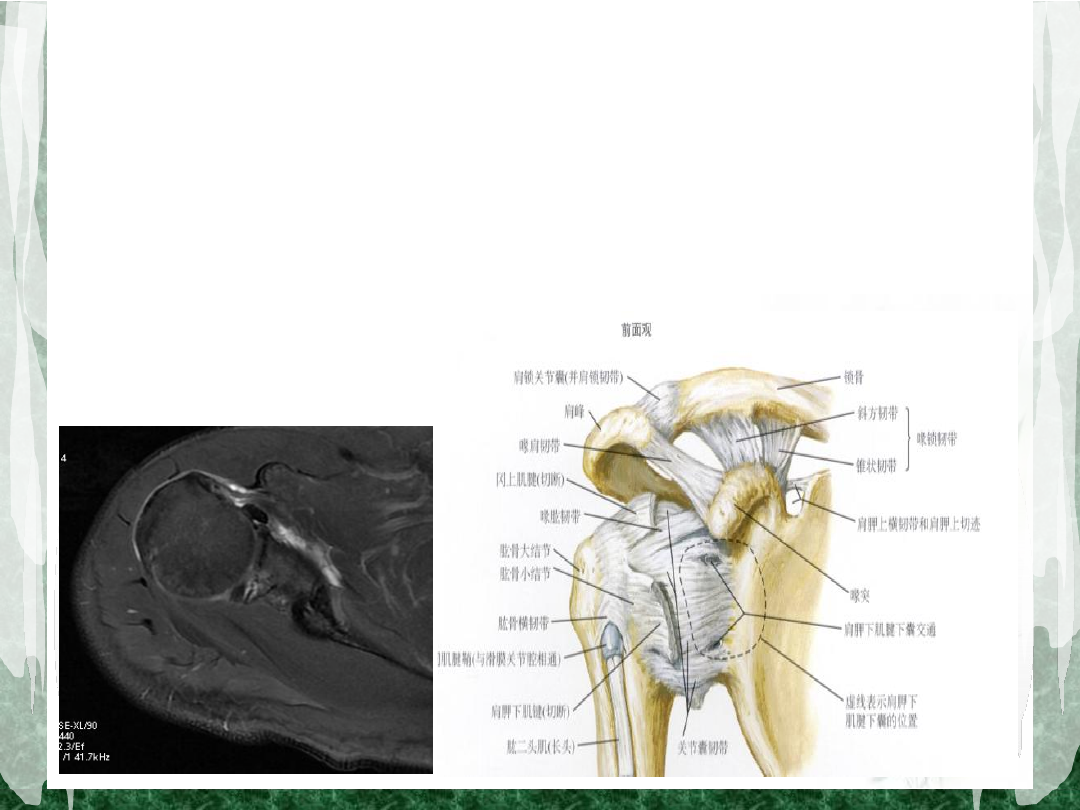

肩袖解剖(一)

•

组成:冈上肌、冈下肌、小圆肌及肩胛下肌

肩袖解剖(三)

肱二头肌长头腱腱鞘:顶层由冈上肌腱及喙肱韧

带组成,底层由肩胛下肌腱组成。

这种解剖关系提示:肩胛下肌腱撕裂常并发二头

腱长头损伤或脱位